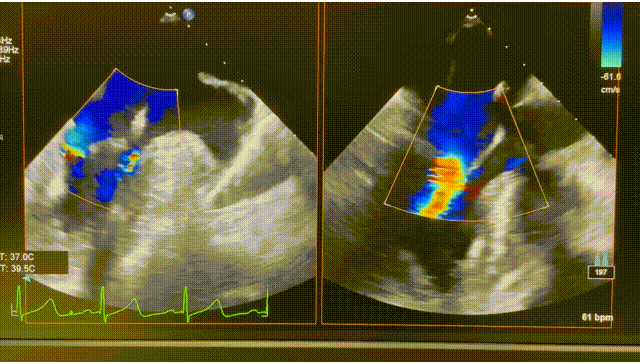

患者为74岁女性。术前心超显示后叶P2脱垂,伴极重度二尖瓣反流(VCW 9mm*16mm),图2。患者全麻后,在超声和射线引导下器械经股静脉穿刺房间隔,通过输送系统送入患者左心房,到达二尖瓣膜反流处,在经食道超声及DSA引导下,术者通过反复评估二尖瓣膜脱垂范围、抓捕位置、反流程度,精准夹合,成功植入1枚ValveClasp瓣膜夹。术后即刻左房压力及V波减低,患者反流从5+减少到1+(图3),跨二尖瓣平均压差3mmHg,肺静脉逆流消失,血流动力学改善明显,手术取得圆满成功。

图3 术后心超图。